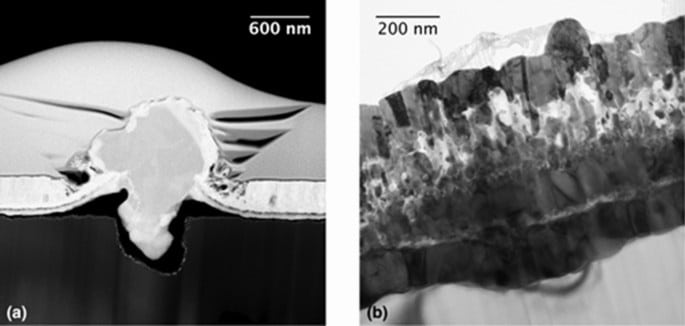

“Χρησιμοποιήσαμε έναν τρισδιάστατο εκτυπωτή για να παράγουμε δείγματα πορώδους σιδήρου-σιλικόνης από σκόνη. Τα δείγματα είχαν αυθαίρετο σχεδιασμό κατάλληλο για τις προβλεπόμενες δοκιμές των μηχανικών και βιολογικών ιδιοτήτων τους. Σκοπεύουμε να παράγουμε εμφυτεύματα ανατομικού σχήματος για δοκιμές σε ζώα”, εξήγησε ο Stanislav Evlashin, κύριος ερευνητής. Η ομάδα ερεύνησε τις μηχανικές ιδιότητες του κράματος για να καθορίσει πόσο καλά τα εμφυτεύματα θα άντεχαν τη συμπίεση και την επέκταση, σε σύγκριση με τον καθαρό σίδηρο και τα άλλα κράματα του μετάλλου που χρησιμοποιούνται ήδη για το σκοπό αυτό. Τα δείγματα πυριτίου-σιδηρού αποδείχθηκαν ανώτερα από εκείνα που κατασκευάζονται από καθαρό σίδηρο και τα άλλα κράματά του. «Δείξαμε επίσης ότι τα εμφυτεύματα θα αποσυντεθούν όπως αναμενόταν με την πάροδο του χρόνου», πρόσθεσε η Bondareva. «Χαρτογραφήσαμε επίσης τη στοιχειακή σύνθεση των δειγμάτων», σημείωσε ο Evlashin. “Η σκόνη που χρησιμοποιούμε για την εκτύπωση περιέχει σίδηρο και πυρίτιο σε μια ορισμένη αναλογία, και υπάρχει πάντα κάποια οξείδωση όταν εκτυπώνουμε σε υψηλή θερμοκρασία με λέιζερ. Έτσι, προκειμένου να βεβαιωθούμε ότι οι μηχανικές ιδιότητες είναι λίγο πολύ οι ίδιες σε οποιαδήποτε σημείο στο δείγμα, έπρεπε να επιβεβαιώσουμε ότι η αναλογία μεταξύ των δύο συστατικών στοιχείων -και του οξυγόνου επίσης- ήταν σωστή και ομοιόμορφα κατανεμημένη σε όλο το δείγμα.”